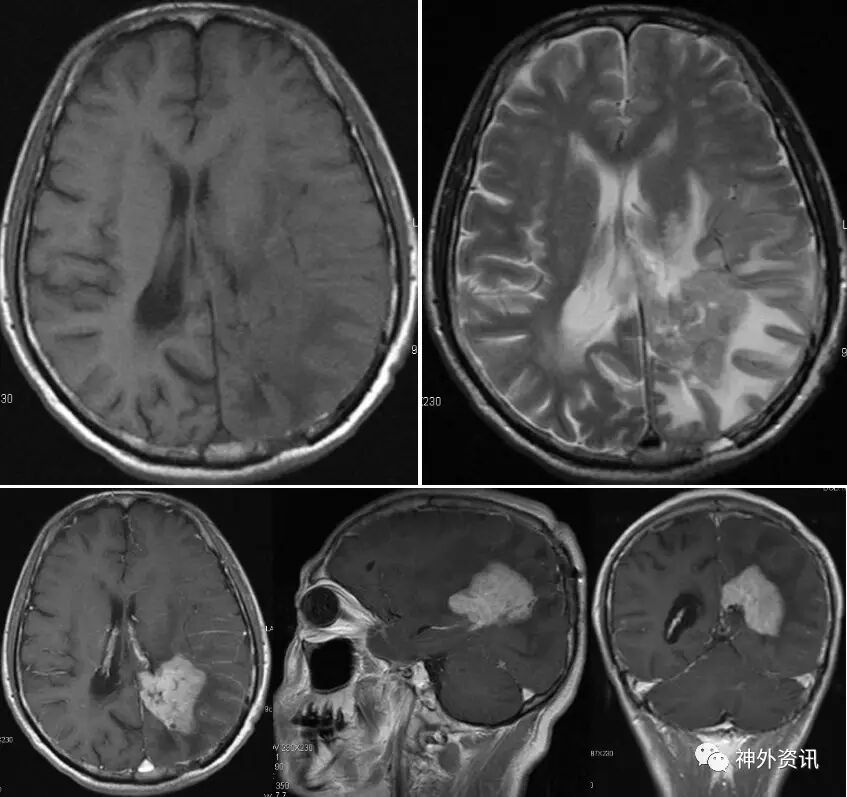

辅助检查:增强MRI示(2016.7.12):左侧顶枕骨术后改变,左侧脑室后角旁不规则形异常信号,大小约37mm*46mm*39mm,呈T1、T2等信号,内见小片T2稍高信号,增强后呈明显强化,强化尚均匀,周边见大片T1低信号、T2高信号水肿区,左侧颞叶及右侧脑室后角旁见小片类似强化信号,左侧侧脑室受压,双侧脑室前后角旁及半卵圆中心、左侧额叶见多发点片状长T2高信号。影像诊断:左侧顶枕骨术后改变,左侧脑室后角旁旁、左侧颞叶、右侧脑室后角旁淋巴瘤复发。两侧脑室前后角旁及半卵圆中心多发缺血灶。左侧额叶囊性病变(图3)。血化验未见明显异常。浅表淋巴结超声、胸片、心电图等相关检查均未见明显异常。

图3. MRI检查:左侧脑室后角旁不规则形异常信号,大小约37mm*46mm*39mm,呈T1、T2等信号,增强后呈明显强化,强化尚均匀,周边见大片T1低信号、T2高信号水肿区。